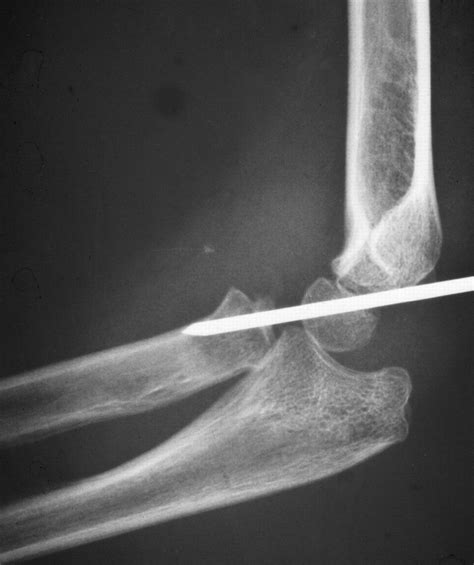

• Imaging Tests: X-rays, MRI, or CT scans to visualize the bone and surrounding tissues and confirm the diagnosis.

• radial head subluxation x ray